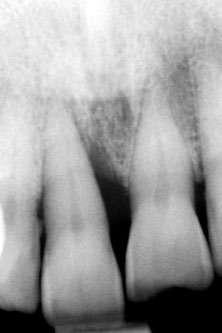

laterales se ponen de manifiesto aún más varias lesiones de esmalte que indican la parafunción en el paciente, unido a los desgastes excesivos en varias zonas (figuras 3 y 4). El paciente acude por dolor y movilidad en la pieza 11, que se ha incrementado en los últimos días, además de sensación de “diente crecido” que como podemos ver en las fotografías iniciales es real, ya que el diente se encuentra ligeramente extruido en relación con el contralateral. Estos signos parecen indicarnos una fractura o fisura. En la fotografía oclusal, podemos observar el desplazamiento del diente debido a la movilidad (figura 5). Posteriormente se realiza un sondaje positivo de la pieza, que lleva a 11 mm por lo que se confirma la sospecha de fractura y se procede a la exodoncia del diente, realizándose una regeneración posterior del alveolo con PRGF-Endoret y

Figura 5. Toma oclusal donde se hace evidente el desplazamiento del diente por el que consulta el paciente, que parece indicarnos una gran pérdida ósea a ese nivel.

Figura 6. Corte seccional de planificación del implante donde observamos el volumen óseo regenerado y la disposición del implante que se va a insertar por delante de la desembocadura del nervio incisivo.

El paciente continúa en seguimiento posterior, con revisiones cada 6 meses durante los dos primeros años. En todas ellas no existe complicación ni pérdida ósea asociada al implante, tal como podemos ver en la radiografía de control a los dos años (figura 18).

Figura 14. Radiografía tras la colocación de la prótesis provisional de carga inmediata.

Figura 17. Radiografía tras la colocación de la prótesis definitiva.

Figura 18. Radiografía de control a los dos años, donde observamos el implante y la estabilidad del tratamiento.

Cinco años después, llevamos a cabo un nuevo cone-beam y en el podemos observar la evolución del implante y de la sobre-corrección vestibular llevada a cabo en la cirugía inicial. Tanto el implante como el hueso que se ha formado a nivel vestibular fruto del injerto empleado está estable y se mantiene sin pérdida ósea asociada, tal como mostramos en los cortes del cone-beam

inicial y final a los 5 años de seguimiento (figura 19). En las imágenes intraorales tomadas en este punto del seguimiento se constata el éxito del tratamiento (figuras 20 y 21). En la radiografía periapical, observamos con mayor detalle la regeneración del tejido óseo del diente en posición 11 así como la estabilidad ósea del implante (figuras 22 y 23).

Figura 19. Imagen inicial del cone-beam y final con el implante cargado a los 5 años de seguimiento con la estabilidad del implante y del hueso generado mediante el injerto

Figuras 22 y 23. Radiografía periapical inicial y a los 5 años de seguimiento.